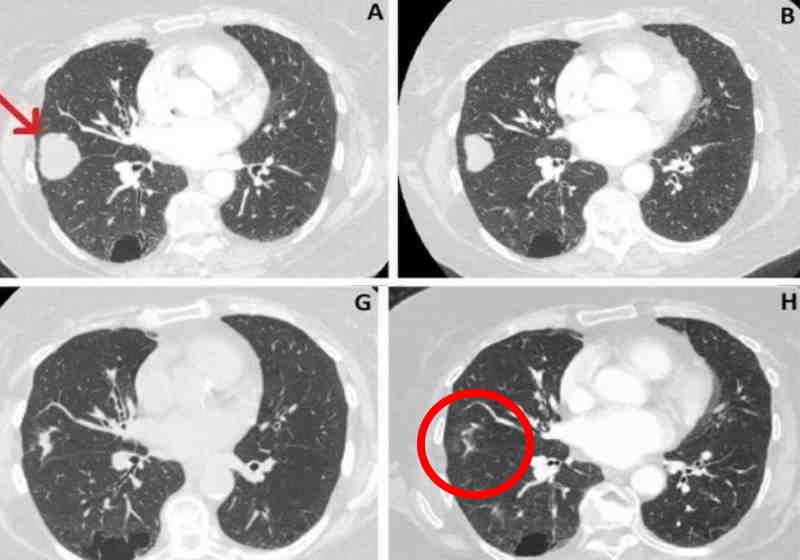

Após receber tratamento com canabidiol (CBD), o tumor no pulmão direito de uma idosa de 80 anos do Reino Unido reduziu 76%.

O câncer foi descoberto em junho de 2018, com 41 mm. Em março deste ano o tamanho era de 10mm.